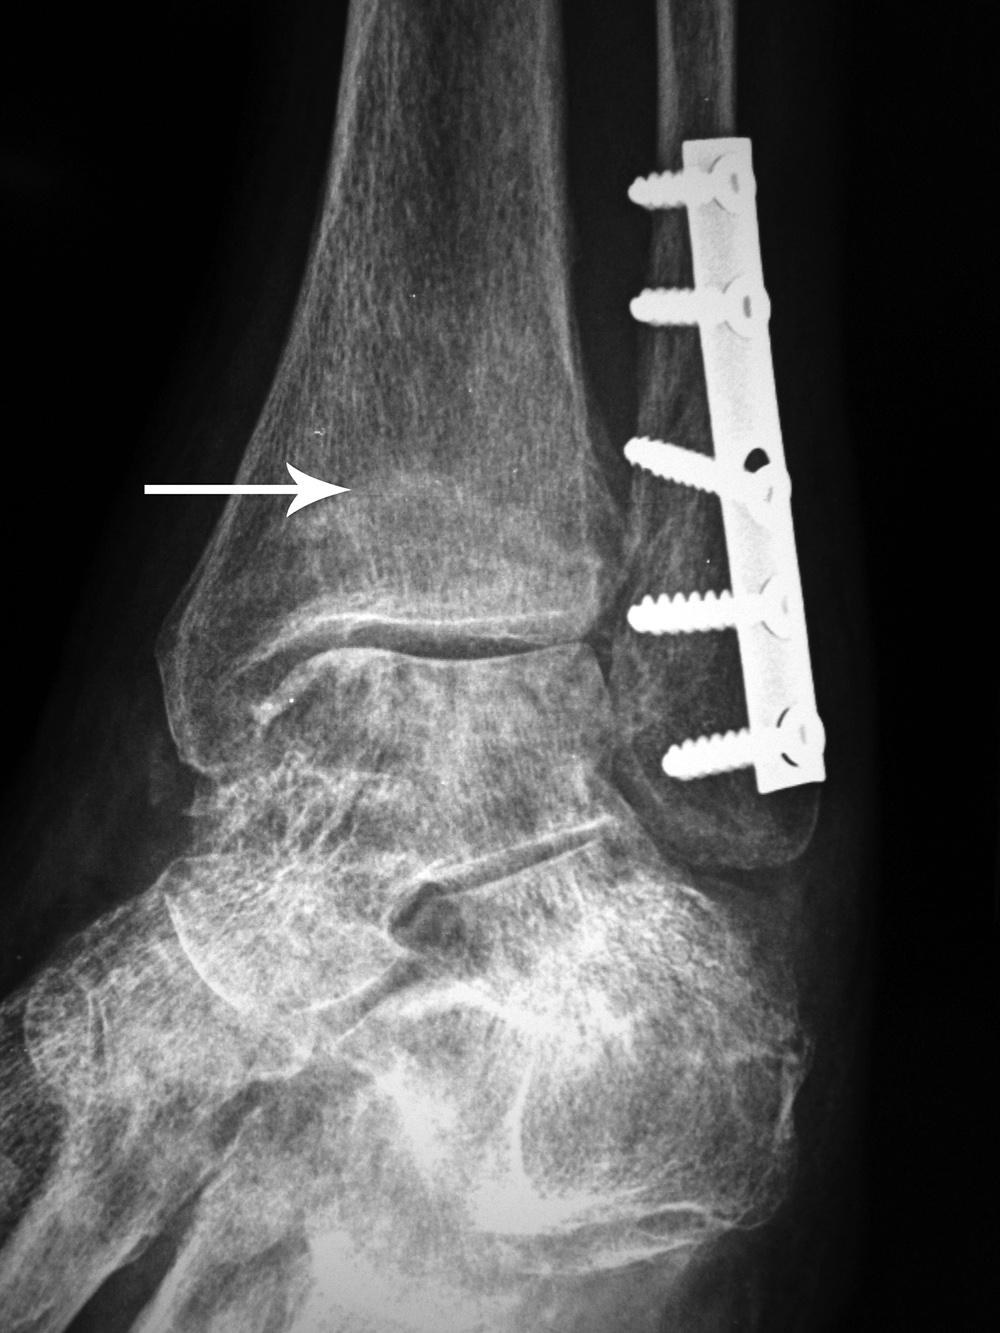

A short one-third tubular plate and screws plus interfragmentary screw stabilize a healing distal fibular fracture. An associated stress fracture (arrow) is in the distal tibial metaphysis from altered weight-bearing from the fibular fracture. |